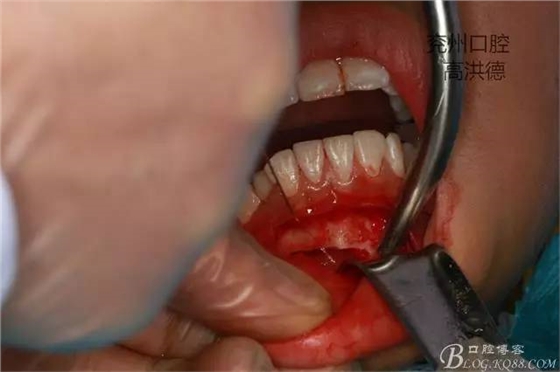

前庭溝做切口,用骨膜剝離器分離粘骨膜暴露骨皮質(zhì)。

45度手機(jī)

去骨,注意避免損傷切牙牙根。